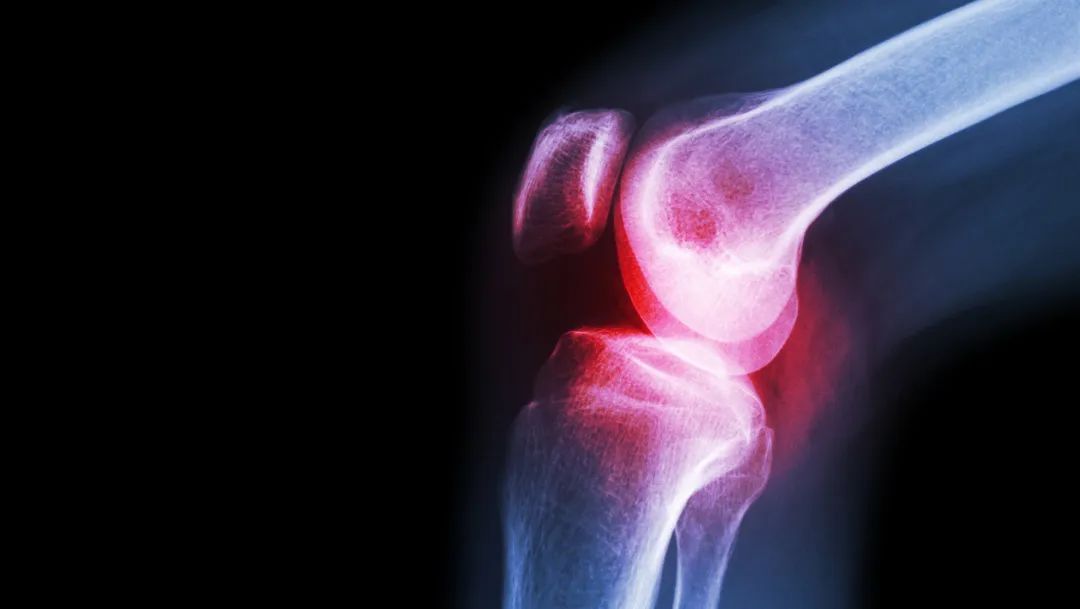

血里尿酸水平升高,会以尿酸盐结晶形式在身体各个关节沉积,沉积到一定程度,就可能引起痛风关节炎发作。痛风的诱发因素包括暴饮暴食、着凉、劳累、剧烈运动、熬夜、喝水少、大量吃水果喝果汁等。

不是只有大脚趾疼痛才是痛风的典型症状,事实上全身关节都可以发生痛风,包括各个脚趾关节、踝关节、膝关节、手指关节、腕关节、肘关节等,甚至耳朵上都会有痛风石。有些高尿酸血症患者没有关节痛症状,但是会有肾脏结晶、甚至是肾结石,也要引起注意。